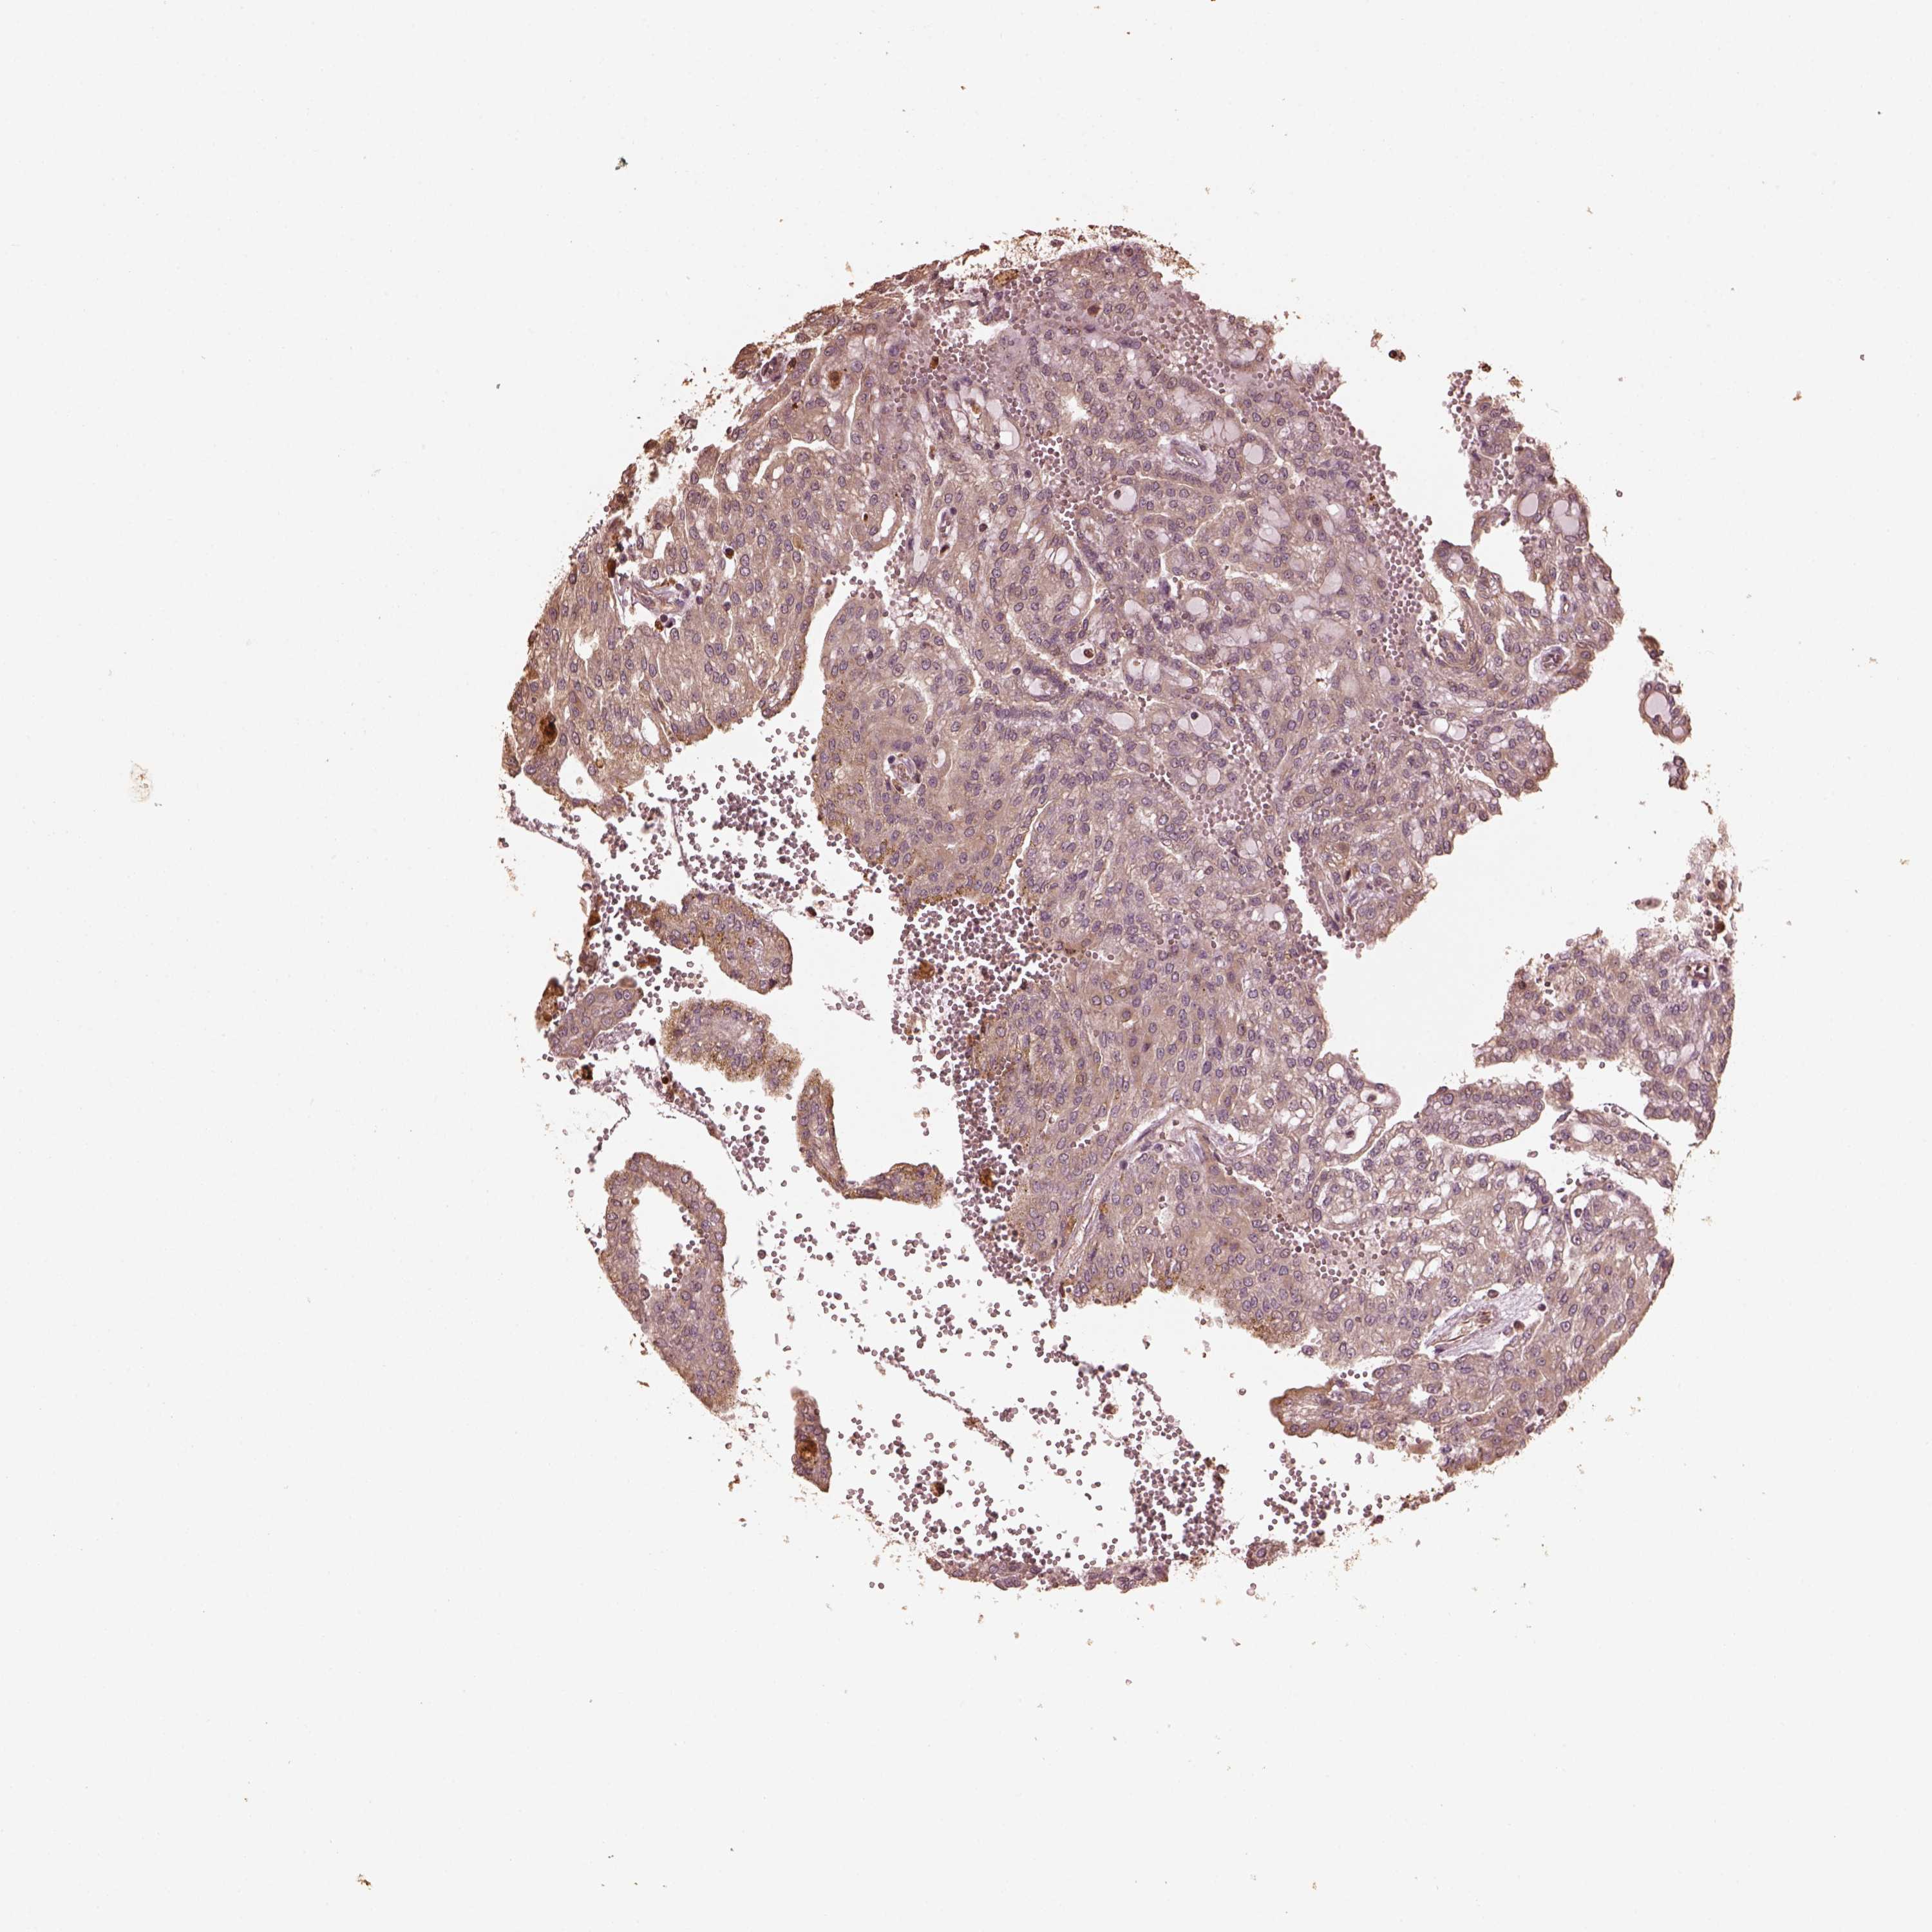

KIDNEY RENAL CLEAR CELL CARCINOMA (TCGA) - Interactive survival scatter ploti

The Survival Scatter plot shows the clinical status (i.e. dead or alive) for all individuals in the patient cohort, based on the same data that underlies the corresponding Kaplan-Meier plots. Patients that are alive at last time for follow-up are shown in blue and patients who have died during the study are shown in red.

The x-axis shows the expression levels (FPKM) of the investigated gene in the tumor tissue at the time of diagnosis. The y-axis shows the follow-up time after diagnosis (years). Both axes are complimented with kernel density curves demonstrating the data density over the axes. The top density plot shows the expression levels (FPKM) distribution among dead (red) and alive patients (blue). The right density plot shows the data density of the survived years of dead patients with high and low expression levels respectively, stratified using the cutoff indicated by the vertical dashed line through the Survival Scatter plot. This cutoff is automatically defined based on the FPKM cutoff that minimizes the p-score. The cutoff can be changed by dragging the vertical line or by entering a cutoff value in the square labeled "Current cut-off".

Under the Survival Scatter plot the p-score landscape (black curve; left axis) is shown together with dead median separation (red curve; right axis). Dead median separation is the difference in median mRNA expression between patients who have died with high and low expression, respectively. It is calculated as follows: median FPKM expression of dead patients with high expression - median FPKM expression of dead patients with low expression. This is intended to aid the user in visually exploring custom cutoffs and the associated p-scores and dead median separation.

Individual patient data is displayed and can be filtered by clicking on one or more of the category buttons on the top of the page. Categories describing expression level and patient information include: high, low, alive, dead, female, male and tumor stages. The scale of the x-axis can be toggled between linear and log-scale by clicking on the "x log" button. Mouse-over function shows TCGA ID, patient information and mRNA expression (FPKM) for each patient.

& Survival analysisi

Kaplan-Meier plots summarize results from analysis of correlation between mRNA expression level and patient survival. Patients were divided based on level of expression into one of the two groups "low" (under cut off) or "high" (over cut off). X-axis shows time for survival (years) and y-axis shows the probability of survival, where 1.0 corresponds to 100 percent.

GTPBP1 is not prognostic in Kidney Renal Clear Cell Carcinoma (TCGA)

Best expression cut offi

Based on the FPKM value of each gene, patients were classified into two groups and association between prognosis (survival) and gene expression (FPKM) was examined. The best expression cut-off refers the FPKM value that yields maximal difference with regard to survival between the two groups at the lowest log-rank P-value. Best expression cut-off was selected based on survival analysis .

When clicking on this number, the vertical dashed line indicating cut-off, the interactive survival plot, and the Kaplan-Meier curve will be adjusted to show results based on the best expression cut-off.

: 14.39

P scorei

Log-rank P value for Kaplan-Meier plot showing results from analysis of correlation between mRNA expression level and patient survival.

N/A

TCGA RNA samplesi

RNA-seq data is reported as average FPKM (number Fragments Per Kilobase of exon per Million reads), generated by the The Cancer Genome Atlas (TCGA) .

Normal distribution across the dataset is visualized with box plots, shown as median and 25th and 75th percentiles. Points are displayed as outliers if they are above or below 1.5 times the interquartile range. FPKM values of the individual samples are presented next to the box plot.

Average pTPM 16.1

Number of samples 521